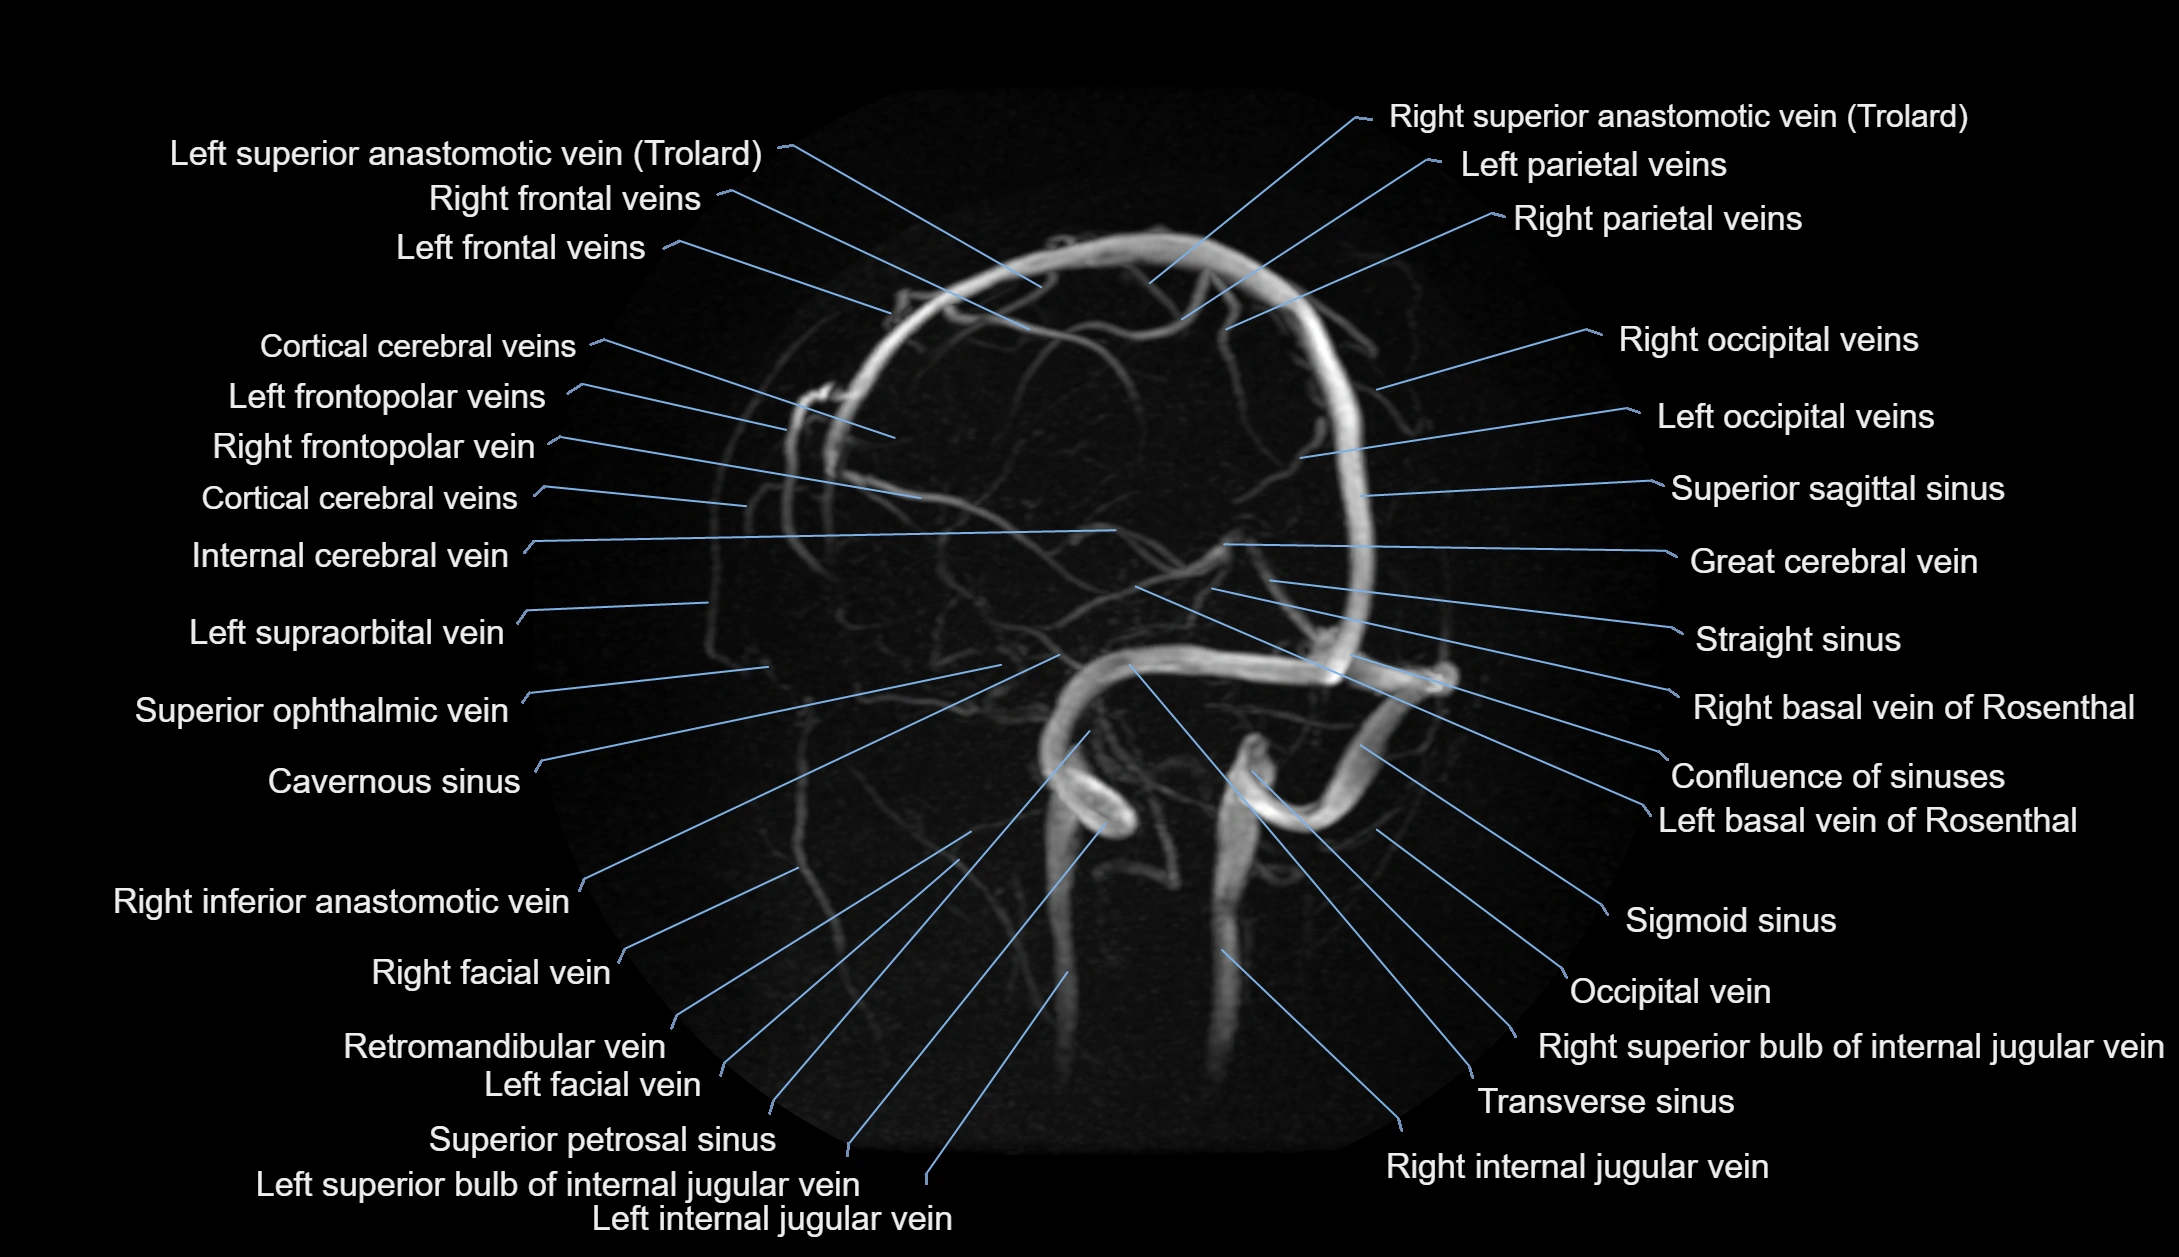

MRI images

image